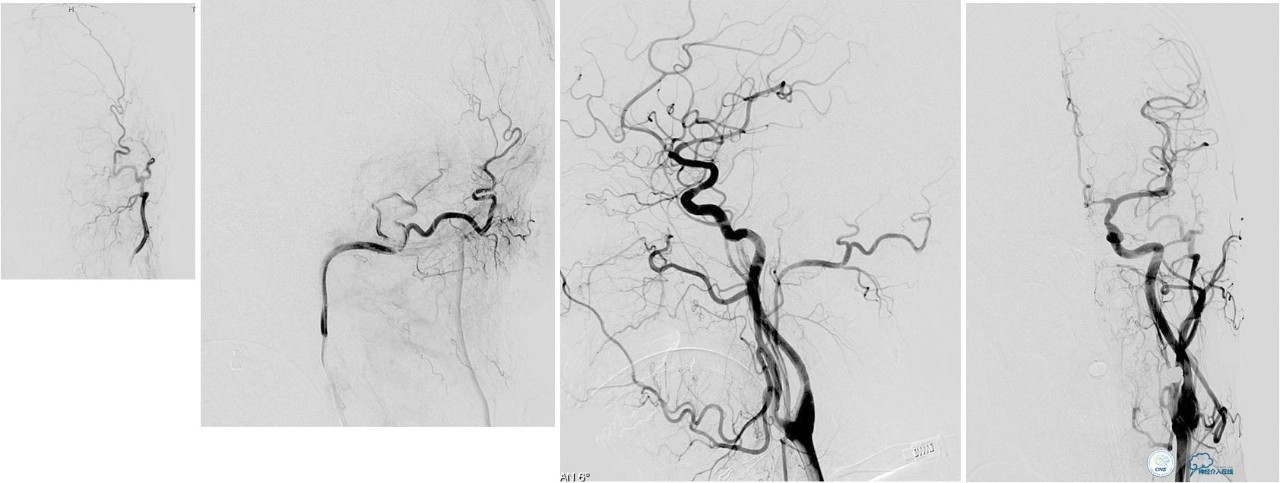

脑膜后动脉供血的小脑幕的瘘。

颈内不参与供血。

大脑后动脉有细小分支供血。

Sceptor球囊无法到达瘘口位置,放在主干内,充盈球囊后把动脉血管床内血液冲洗干净,形成楔入效果。

术后造影【Post embolization】